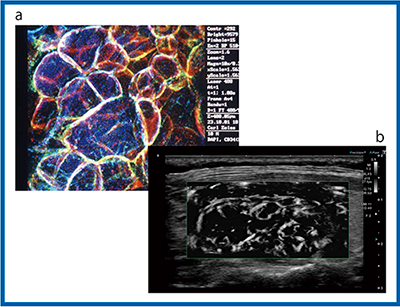

2)Superb Micro-vascular Imaging:SMI

より低速な血流を描出できるSMIでは,装置の性能が向上することで血管の描出能の違いがより明確にわかる。図8は,color-coded SMI(cSMI)でカラー表示された血流の画像だが,Aplio i800(b)では通常の血流に加えて,腫瘍の内部まで入り込むような微細な血管の様子まで確認することができる。また,血流信号をモノクロで表示したmonochrome SMI(mSMI,図9)の場合,Aplio i800(b)では濾胞構造を示す腫瘍の周囲の血管構造まで確認できるほど低流速の血流が描出されている。

濾胞性腫瘍の血管構築は,良性では類円形の血管走行できれいな濾胞を描いているが,癌腫ではイレギュラーに網目状に発達した構造を示す。癌腫は進行するにしたがって主要血管網の中心を貫通する血管が認められ,カラードプラにて悪性を疑う濾胞内部の拍動性の血流と類似する。図9 bのAplio i800のmSMIの画像は,甲状腺濾胞の周囲を囲む類円形状の血流を描出しているとも考えられる。さらに高精細な血流の描出が可能になれば,SMIによって癌腫の複雑な網目状の血管構造が描出できることが期待される(図10)。

図8 cSMIによる充実性腫瘍の描出能の比較(12MHz)

a:Aplio 500 b:Aplio i800

図9 mSMIによる充実性腫瘍の描出能の比較(12MHz)

図10 SMIによる濾胞性腫瘍の描出

a:共焦点レーザー顕微鏡像* b:mSMI

(*伊藤病院・佐々木栄司氏提供)